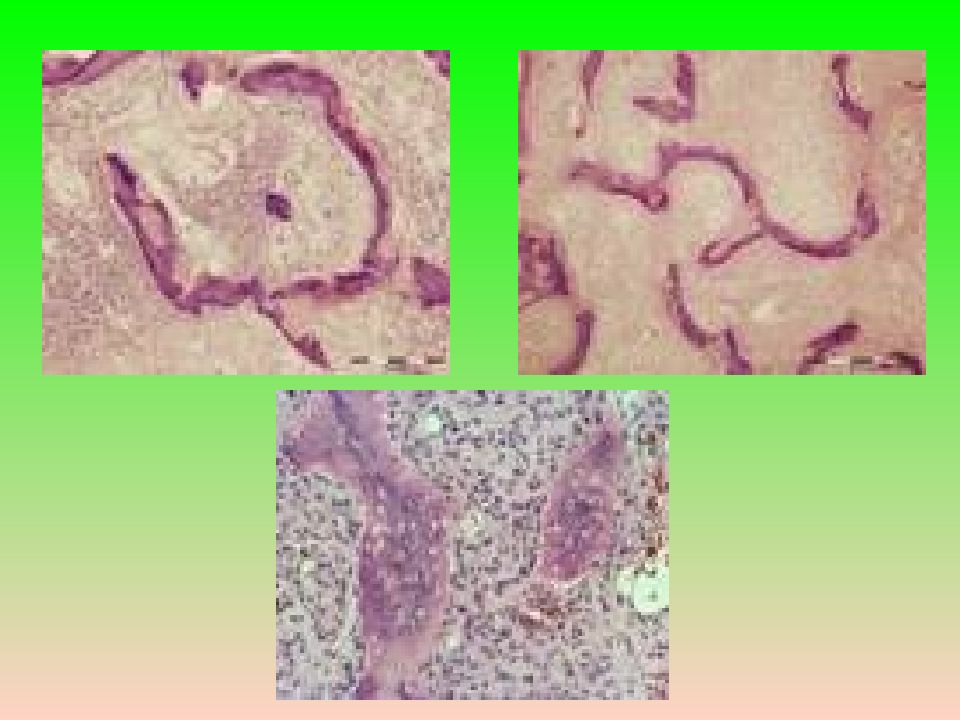

Слайд 12: Микроскопия

Соединительнотканная строма с костными трабекулами примитивного строения, миксоидными изменениями, иногда формируются структуры типа цементом, очаги хондроидной ткани, кисты. Костные трабекулы лишь иногда ограничены остеобластами. Цитологическая атипия и митозы не характерны. В очень редких случаях может наблюдаться атипизм клеток, связанный с дегенеративными или регрессивными изменениями. Микроскопия